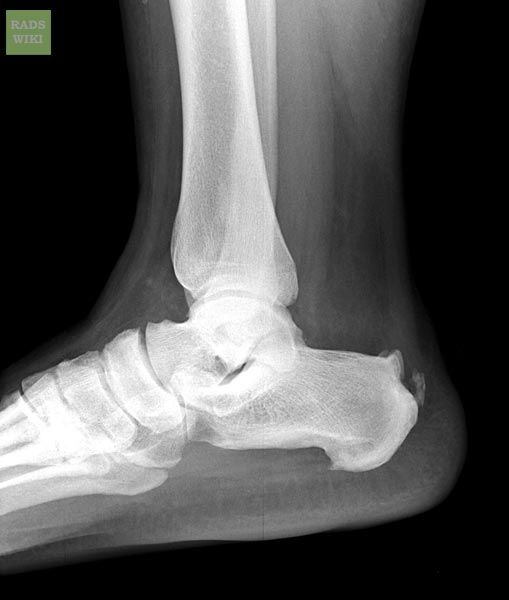

Topuk dikeni, topuk kemiğinde gelişen sivri uçlu kemik büyümeleridir. Kalkaneus olarak adlandırılan topuk kemiğinin altında kalsiyum birikintilerinin oluşturduğu dikene benzeyen yapıdır. Röntgen filmi ile kolayca topuk dikeni teşhisi konulabilir bu genelde 1 – 1,50 cm lik bir kemik görünümündedir. Eğer röntgende görünmüyorsa bu tarz durumlara topuk dikeni sendromu adı verilmektedir.